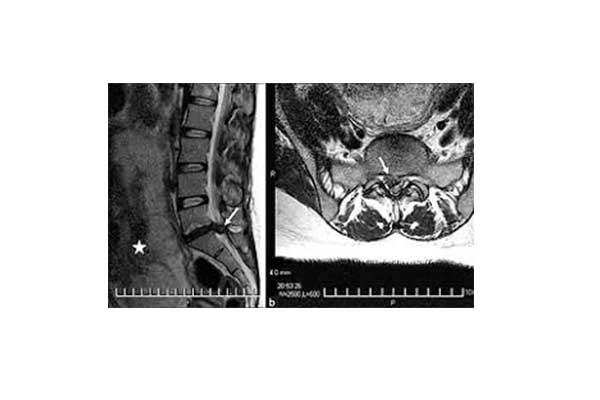

- Magnetic Resonance Imaging: It usually provides the most detailed information on whether or not a herniated disc is present, its location and size, as well as the compressive effects it causes. It is often performed for preoperative planning. It helps to rule out spinal stenosis.

When the patient suffers from a symptomatic herniation of the intervertebral disc, the disc itself is not painful. On the contrary, the material (nucleus pulposus) that collapses or leaks from inside the disc presses and irritates the closest root of the nerve exiting the spinal cord. This injury produces a feeling of pain called radical pain. Beyond the lumbar region (back pain) it also reflects on other parts of the body and especially the lower extremities. In the case of the nerve roots that make up the sciatic nerve, it is called sciatica.

When repetitive axial pressure is applied to the spine, the disc and especially the fibrous ring may rupture or crack. In the lumbar spine, the protrusion of the disc can lead to pressure effects on the closest root of the spinal nerves. In addition, the leaking material can irritate the nerve. This can cause local inflammation. The result is an acute feeling of pain that reflects from the lumbar spine to the buttocks and lower limbs. Finally, it is important to note that disc degeneration (discitis) is not necessarily a progressive condition per se. It does not always lead to an intervertebral disc hernia.

The loss of bladder control (urinary incontinence) or intestine control (fecal incontinence), as well as numbness in the back of both thighs with concomitant weakness in the lower limbs are symptoms of the Cauda Equina syndrome. This is a serious and urgent pathological condition. It is caused by a large hernia that presses on the nerve roots coming out of the medullary cone (Cauda Equina). The patient must be treated surgically within 48 hours in an effort to reverse the neurological damage.